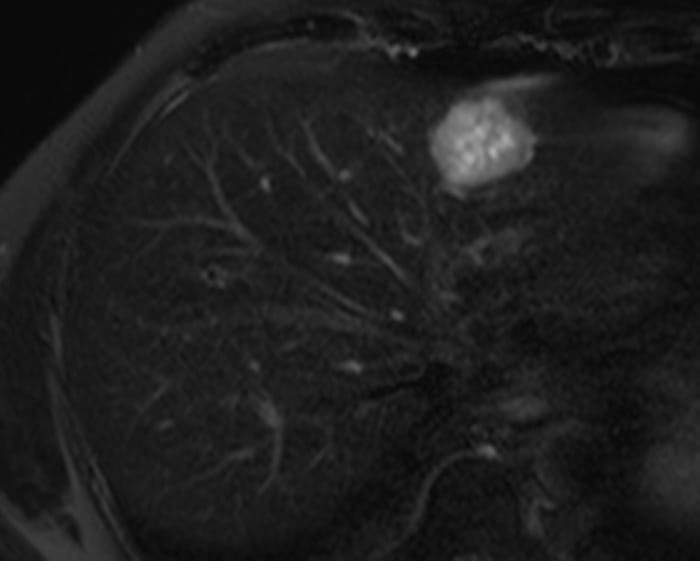

Ung thư đường mật

» Thông tin: Nam giới – 57 tuổi.

» Lâm sàng: Đau bụng.